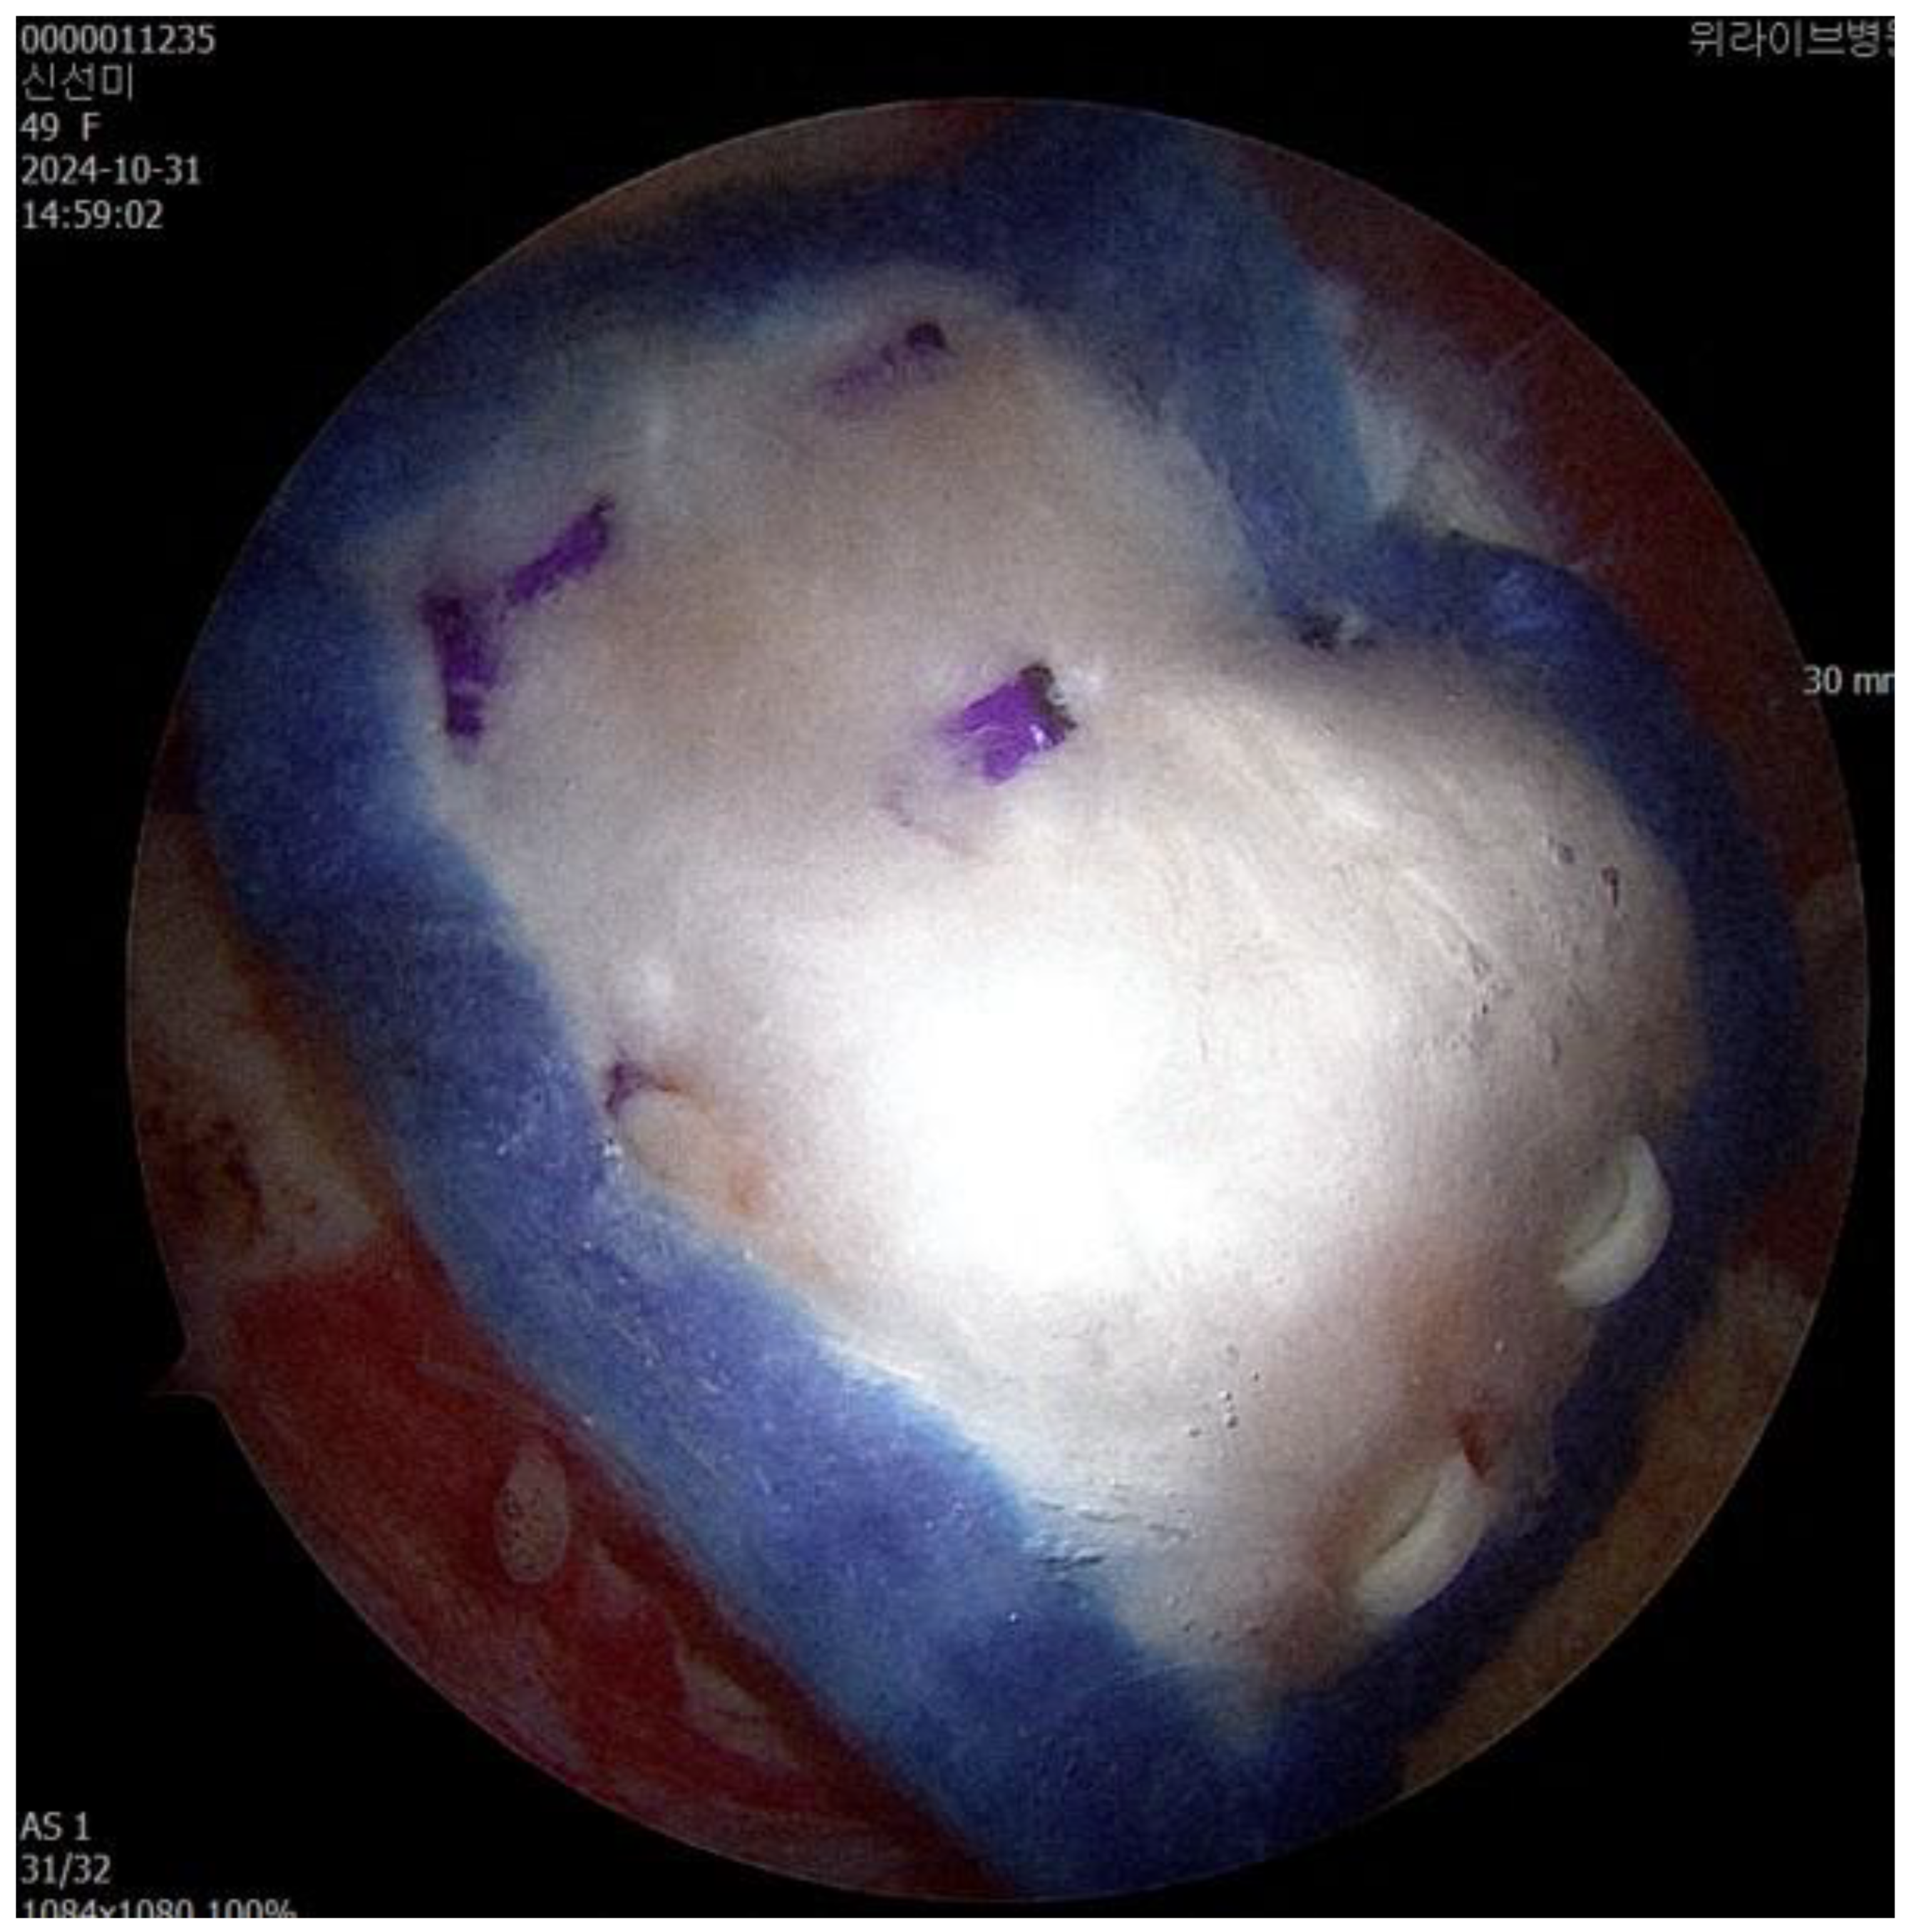

The surgeon identified a bursal-side partial-thickness rotator cuff tear and carefully examined the lesion to rule out full-thickness involvement (Fig. 1A). To preserve native rotator cuff, frayed tendon tissue was selectively removed using a shaver and radiofrequency alation device. Afterward, the coracoacromial ligament was released and acromioplasty was performed with a burr and high-speed shaver to address the acromial spur, which contributes to subacromial impingement and tendon degeneration [13].

After establishing a superior anchor portal, a lateral working portal was created for insertion of the Bioinductive Collagen Implant (REGENETEN, Smith & Nephew, London, UK). Using the manufacturer-provided delivery system, the implant was deployed directly onto the degenerative rotator cuff tissue and secured in position. Final arthroscopic assessment confirmed stable positioning and adherence of the implant prior to closure (Fig 1B).

Figure 1. (A) Bursal side partial thickness supraspinatus tear was observed. (B) The bioinductive collagen implant is fixed to cover the musculotendinous junction medially and the greater tuberosity laterally.